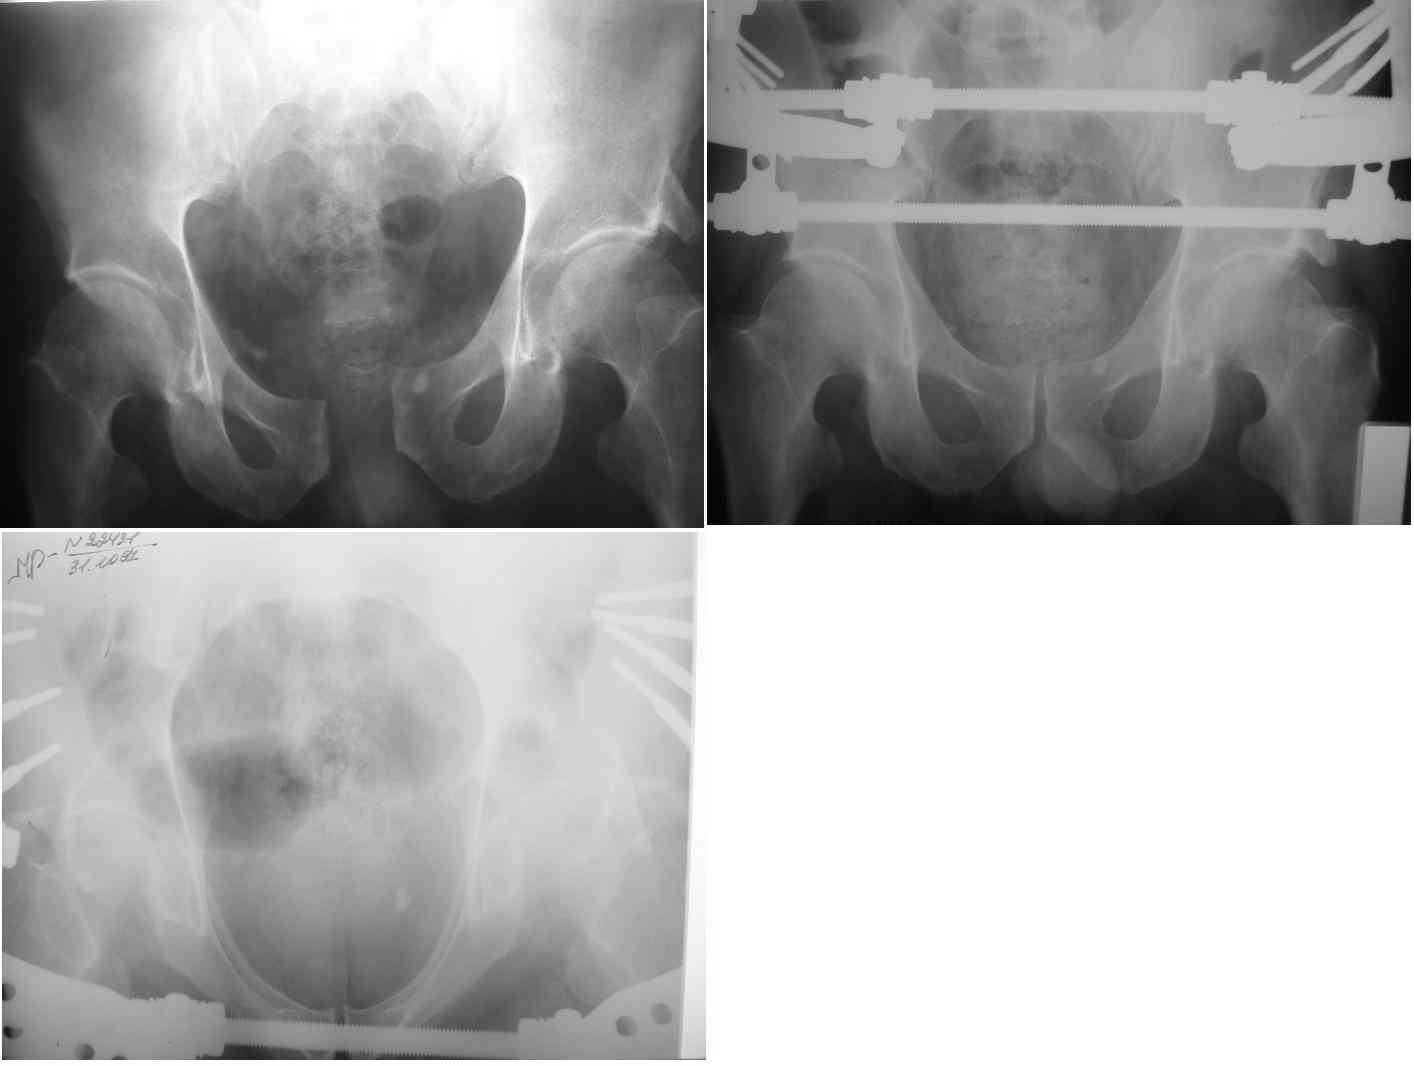

извините за опоздание , вот фотографии

Репозиция действительно очень неплохая, но чтобы уменьшить риск развития поздней нестабильности, в такой ситуации лучше выполнить синтез лонного сочленения пластиной и оставить аппарат месяца на 2.

В представленном случае повреждение несомненно ротационное и реальный диастаз как раз около пограничных 2,5 см, репозиция идеальная, достигнута в первые дни после травмы. Я бы ограничился 3 мес фиксации в аппарате с ограничением нагрузки первый месяц, и функциональными снимками в 6 -8 недель.

В вашем случае при таком диастазе надежнее будет зафиксировать задние и передние отделы(сзади -винты, спереди -пластина).

Вот вариант решения похожей ситуации

Алексей Смирнов,

Нижний Новгород